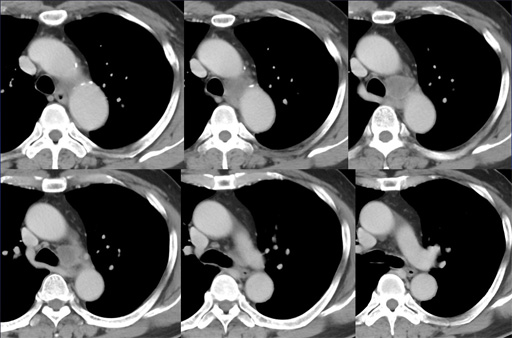

(側面像) 図3 胸部CT 縦隔条件

図3 胸部CT 縦隔条件 図4 胸部CT 縦隔条件

図4 胸部CT 縦隔条件

(thinsection) 図5 胸部CT 縦隔条件